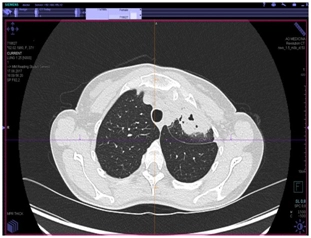

КТ органов грудной клетки (от 17.08.2017 г.)

Заключение: массивные инфильтративные изменения в верхней доле левого легкого полностью неясного генеза, возможно имеет место как воспалительный специфический характер поражения с распадом, так и осложнение пневмонии с формированием абсцесса, злокачественный процесс с распадом мало вероятен.